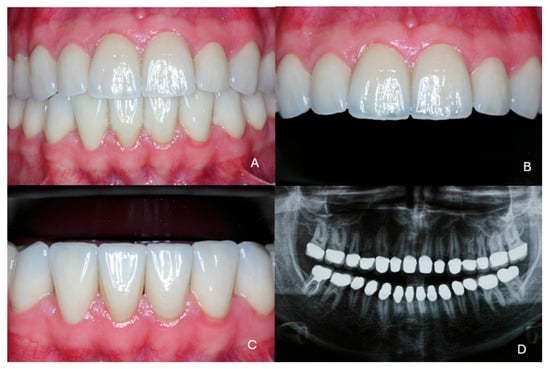

2. Case Presentation